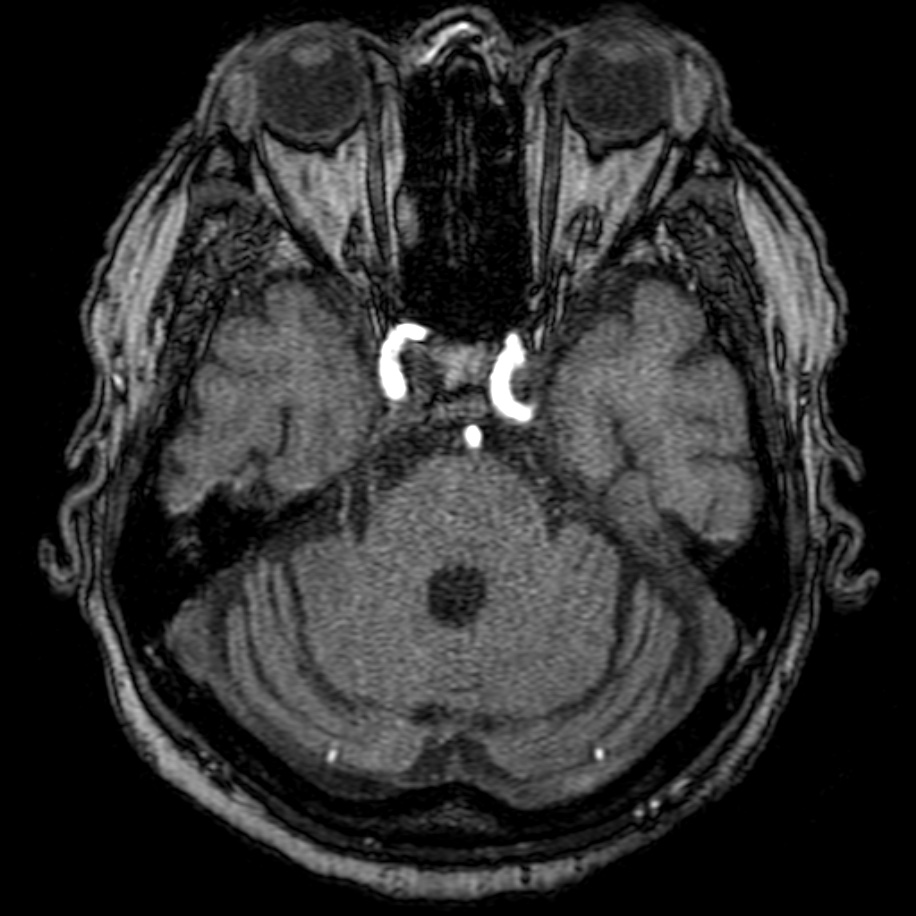

Results: The patient’s BP = 110/70 mm Hg,during the cardiovascular test the arterial pressure did not change.Comprehensive diagnostics of the vestibular analyzer function using computer VNG(videonystagmography)/vHIT at the time of examination-the nystagmus pattern corresponds to vestibulopathy of central genesis-Cerebellar ataxia.Based on the results of an MRI of the brain (3 Tesla),the diagnosis was made:Sporadic adult-onset ataxia; there are signs of isolated cerebellar atrophy in T1 mode

MRI of the brain